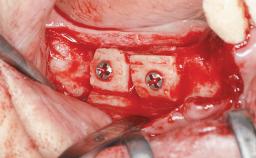

A 20-year-old woman was referred for implant therapy in 2004. Her medical history revealed no significant findings, and neither did she smoke nor take any medications. An extraoral examination revealed no abnormalities of the skin, hair or nails. The intraoral examination revealed only 11 permanent teeth clinically. These were normal in shape, size, and color. In addition, eight retained deciduous teeth (53, 62, 63, 71, 72, 73, 81, 82) were present. No abnormalities were detected during the general examination. The family history revealed that the patient’s father and two sisters were on record with similar conditions. The clinical examination revealed a thick gingival biotype. No recession of the attached gingiva was noted, but the retained deciduous teeth were mobile and unsightly. As a syndrome had not been diagnosed, the case was categorized as non-syndromic oligodontia.

| Bone Augmentation | Horizontal|Staged |

| Augmentation Materials | Autogenous chips|Autogenous block(s)|Membrane |

| Bone Volume | Deficient horizontally, requiring prior grafting |